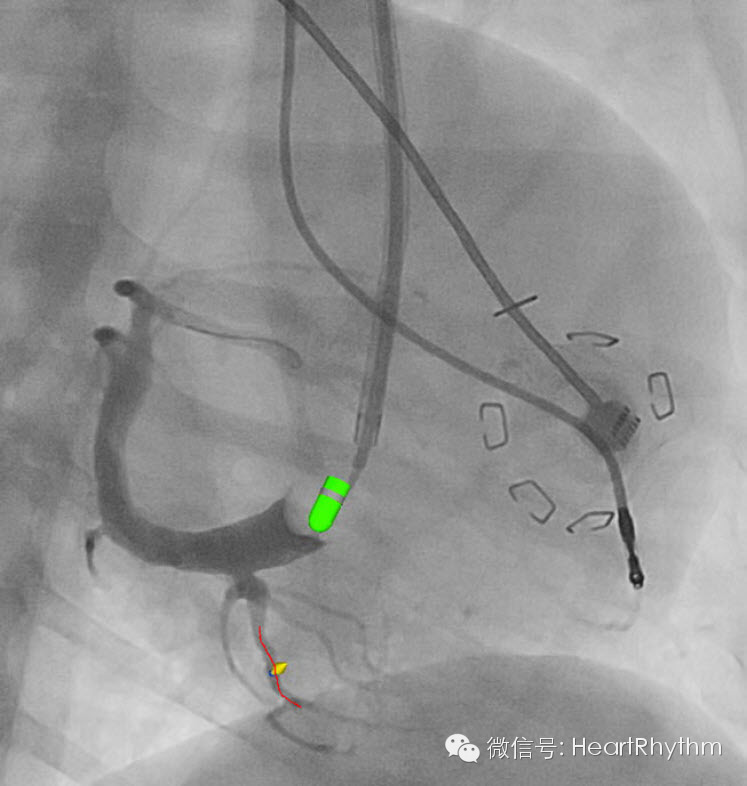

图4. 电极植入位点为4级难度的典型病例,黄色箭头代表传感器图标,红线代表导丝